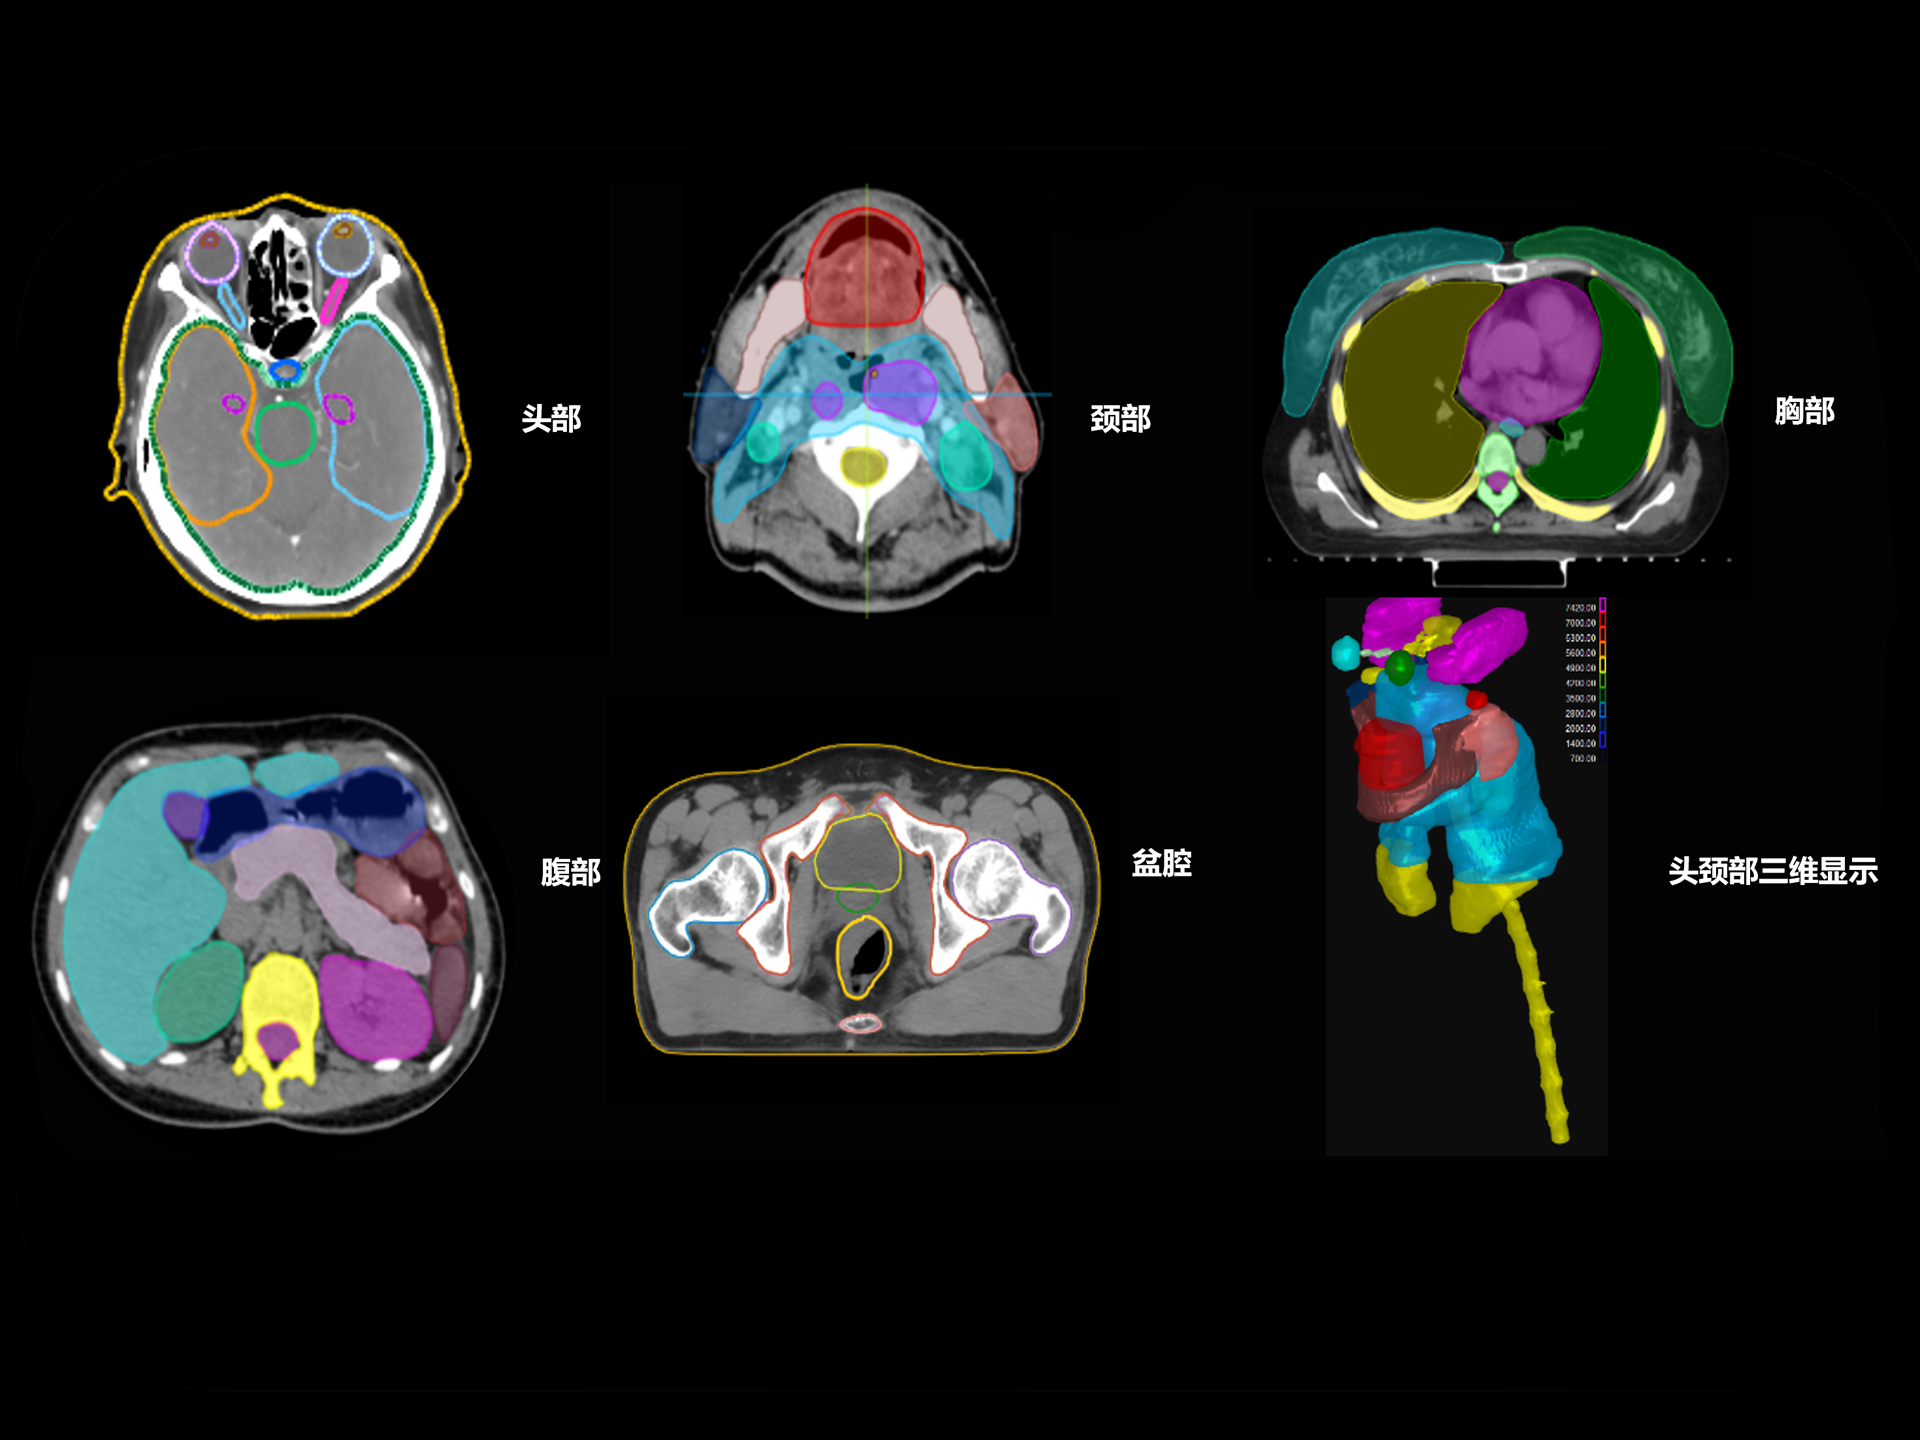

uLinac HalosTx®凭借先进算法与简约设计,提供简单快捷的自动化应用,将复杂的放疗流程自动化、简单化,让您的放疗工作如行云流水般开展,并可支持全身各部位自动化应用,赋能临床智慧体验。

支持CT、MR、PET多模态影像及全身100+器官勾画模型,准确度高、分割速度快、重现性好,提高临床勾画效率与一致性。

亚秒级自动勾画